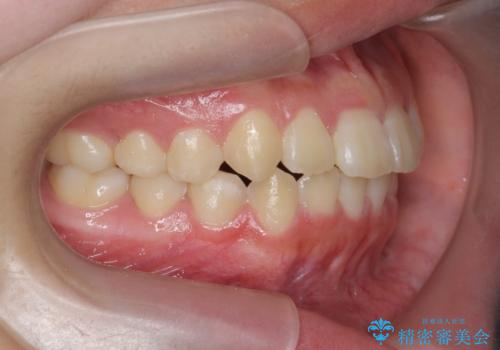

インビザラインで行う八重歯の治療

- 笑った時に目立つ八重歯の矯正治療を求めて来院されました。

マイクロインプラントを用いた臼歯の後方牽引、およびゴムかけ等の付加処置を駆使して八重歯の治療を行っていきます。

しっかりとゴムかけを頑張っていただいたおかげで、上顎臼歯の後方移動が達成されしっかりとした噛み合わせの構築と、八重歯の治療を達成することができました。